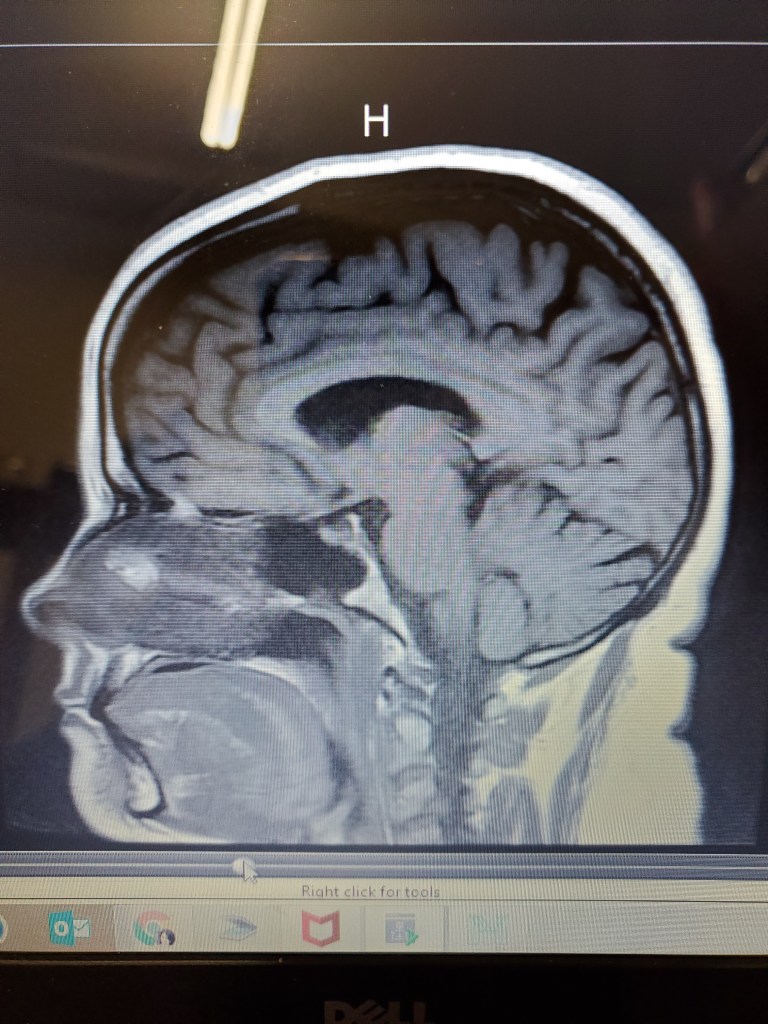

I’ve spent most of my time last week remembering people, mourning a loss of someone near and dear to our family, and reorganizing my room in the process. A few weeks ago, it was a father of a bestie who was diagnosed with Alzheimer’s. This past week, a mother of a different best friend, whom had Dementia.

Your loved ones, who would regularly and normally stay fairly well organized and confident in their function, start to show signs of object permanence, starting to leave things in “convenient” places so they don’t “forget” to do things or use things daily. It actually comes on pretty subtle at first. Then, there is obsessive compulsive behaviors as well coupled with the “convenient” storage of items they need daily. It’s an ugly vicious cycle to lose your cognitive function, and the family has to constantly ask themselves, “Why did they do that?” I’m telling you the why. However, don’t you dare touch their system that they have created, because there will be an argument that ensues, or at least a lot of grumbling, because they’ve lost enough cognitive or memory to remember where it was placed, once you take it out of its position to clean the house again. To be honest, they’re going to forget anyway eventually if you know they don’t use it daily, and they definitely won’t remember it at all if it’s placed in a box next to them, it’s in a box, and it is UNSEEN. “Out of sight, out of mind.”